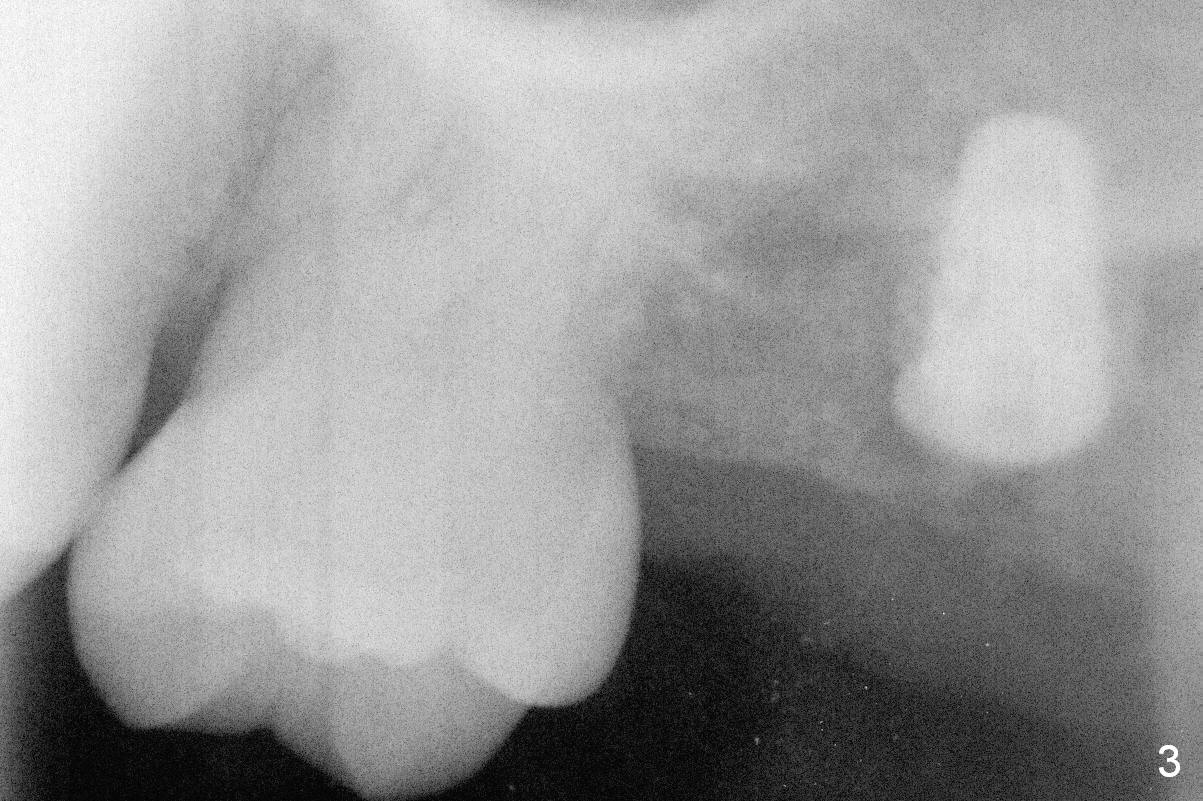

Initial osteotomy at the site of #15 for 4x11 mm dummy implant is created by #15 blade, Magic Split and Magic Expanders (ME) 3.0 and 3.8 mm (flapless, Fig.1,2, 4A (blue circle)). The implant is palatally displaced. Release incision confirms the deviation. A new osteotomy is established with 1.6 mm pilot drill in the middle of the site (Fig.4A (occlusal view) red circle). Distal to the new osteotomy is the incompletely healed socket (brown circle). As the osteotomy is enlarged by ME until 4.3 mm and placement of 4.5 and 5.0 mm dummy implant and of 5.5x9 mm definitive one (Fig.3, 4B large red circle), the osteotomy gradually deviates distopalatally. Introspectively, the new osteotomy should have been placed more buccomesially (Fig.4C red circle) so that the final osteotomy may end up normally (Fig.4D large red circle).

Prior to implant placement, two pieces of PRF plug are inserted. The insertion torque is <15 Ncm. A cover screw is placed. The distopalatal defect is covered by allograft and 1 piece of PRF membrane. There is no intraop sinus membrane perforation or nasal hemorrhage postop.

Because of unfavorable implant/crown ratio (Fig.3), the implant will be uncovered 6-7 months postop. An angled abutment is expected to correct the distopalatal displacement of the implant. In the meantime orthodontic treatment should start to align the malpositioned anterior teeth before extraction and implantation.